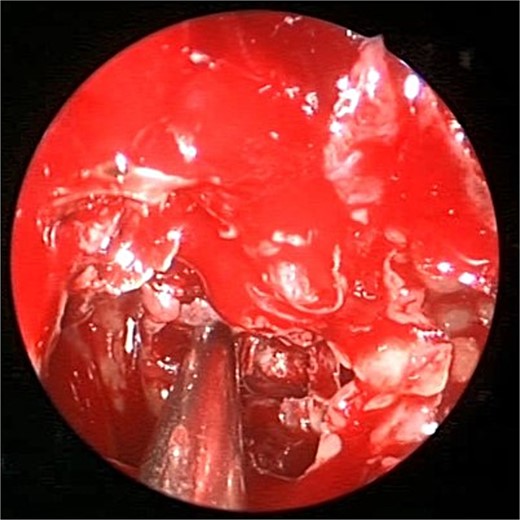

A 69-years-old diabetic female was referred from neurology as she complained of an acute onset severe headache, diplopia, and retro-orbital pressure. An initial CT scan with a subsequent MRI scan (Fig. 5) showed infiltrative sphenoid pathology invading both skull base and cavernous sinus given a provisional diagnosis of acute invasive fungal sinusitis. The patient was urgently taken to the operative theater to endoscopically debride sphenoid sinuses (Fig. 6). Histopathological examination confirmed the diagnosis of invasive sphenoid sinus mucormycosis.

Coronal CT (A) and MRI (B) and CT image guided intra-operative (C) images of the paranasal sinuses showing aggressive sphenoid sinus disease extending to the skull base and cavernous sinus.

Intra-operative endoscopic view of shenoid sinus debridement of invasive fungal disease.